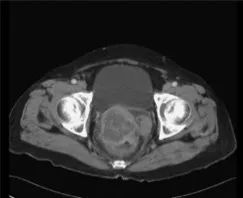

背景:腹腔内硬纤维瘤(DTs)可以和胃肠道间质瘤(GISTs)的复发或进展很相似。对该病的鉴别诊断对于避免不必要或不适当的治疗很重要。病例总结:8例患者均经历了胃肠道间质瘤手术切除,手术切除后诊断腹腔内硬纤维瘤的中位时间为1.8年。腹腔内硬纤维瘤发生部位均在GIST手术部位周围腹膜。以下临床怀疑加上放射学检查结果可有助于诊断腹腔内DTs:(1)在GIST手术部位周围的腹膜出现新的单一病变;(2)在其他病变用伊马替尼控制好的情况下,该病变不受控制;(3)CT显示有明确的卵圆形病变,伴有延迟或轻度强化,无坏死、出血和囊性改变;(4)PET显示轻度或无高代谢活性的病变,与最初的GIST高活性病变相反。除一个不可切除外,所有DTs均手术切除,其中只有一个DTs在另一个腹膜部位复发,也被手术切除。结论:GIST患者新的单一病变应与腹腔内DT进行鉴别诊断。

这是一篇很有意思的病例总结的文章。8例看似胃肠间质瘤术后复发的病例,但Tki药物治疗效果不佳,手术切除活检证实为腹腔内硬纤维瘤(DTs)。我们在临床上经常可以看到,随着GIST患者存活率的延长,这些患者确实可以发生其他原发性恶性肿瘤。尽管GIST与其他恶性肿瘤之间的关联尚不清楚,但各种实体瘤和血液学恶性肿瘤与GIST同时或异时发现的文献已有很多报道。如文章所言,GIST患者发生DT的风险评估明显高于普通人群。大多数DT病例(75%)发生在GIST后,表现类似于GIST的复发或进展,给我们临床医生带来很大的迷惑。如何区分是GIST复发进展,还是DTs?这篇文章给我们提供了很好的经验:(1)在GIST手术部位周围的腹膜出现新的单一病变;(2)在其他病变用伊马替尼控制好的情况下,该病变不受控制;(3)CT显示有明确的卵圆形病变,伴有延迟或轻度强化,无坏死、出血和囊性改变;(4)PET显示轻度或无高代谢活性的病变,与最初的GIST高活性病变相反。但最终切除活检是区分继发性恶性肿瘤和GIST的唯一可行方法。这篇文章提醒我们,在GIST患者出现新的单一病变的情况下,尤其是TKI药物疗效不佳时,除了想到耐药的情况外,应该怀疑到有继发新的肿瘤的可能。考虑到腹腔内DT与GIST的密切关系,DT应作为一种重要的鉴别诊断。为避免不必要或不适当的治疗,腹部DT的诊断和治疗均需手术切除。使用CT或18FDG-PET的临床经验和放射学检查可能有助于手术切除。当然,多学科的会诊,也是有助于我们解决此类问题的得力手段。